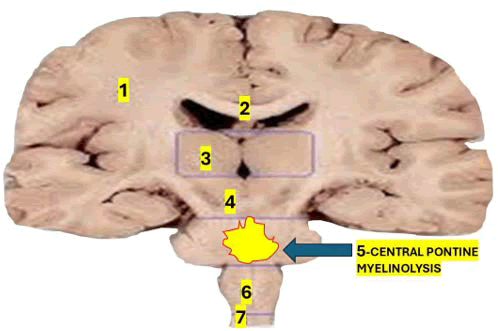

As mentioned before, CPM is an uncommon demyelinating disorder that affects the pontine region of the brainstem, causing LIS in the initial phase [27,28]. Another aetiology of CPM is the fast correction of hyponatremia [29]. The commonest affected area of demyelination at the pontine level is represented in Figure 1.

Figure 1: Shows the affected area in cases presenting CPD. 1) Coronal radiata; 2) Corpus callosum; 3) Thalamic nucleus; 4) Midbrain; 5) Pons; 6) Medulla oblongata; 7) Spinal cord